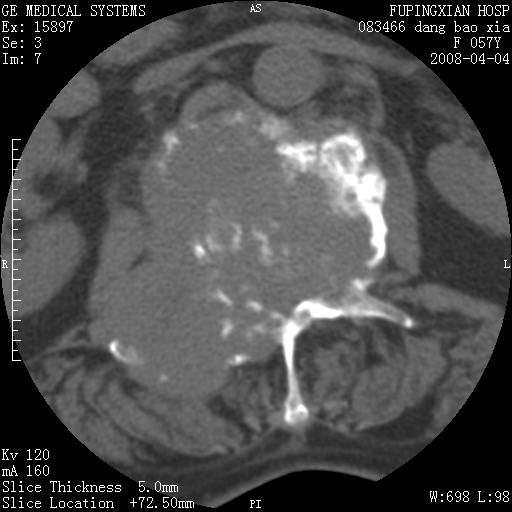

标题: CT12677:女性,57岁,疼痛数月。 [打印本页]

标题: CT12677:女性,57岁,疼痛数月。

椎体及附件骨质破坏同时伴软组织肿块,首先考虑恶性肿瘤。

病灶见多部位;转移瘤

查原发灶吧,考虑转移瘤。老年人出现骨肿瘤首先要除外转移瘤及骨髓瘤。

椎体及附件溶骨性破坏,周围巨大软组织肿块,首先考虑转移瘤。